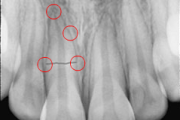

krooni murd paljastunud pulbiga (Mitsuhiro Tsukiboshi,DDS)